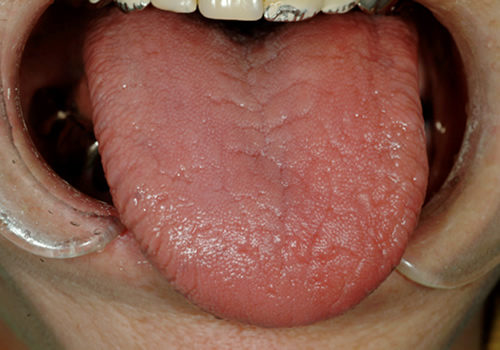

シェーグレン症候群

シェーグレン症候群は、目や口の乾燥症状を認める疾患です。口腔内の唾液分泌量が低下します。自己免疫疾患の一つであり、様々な全身的疾患を合併する場合もありますので、しっかりとした診断を行っておく必要があります。